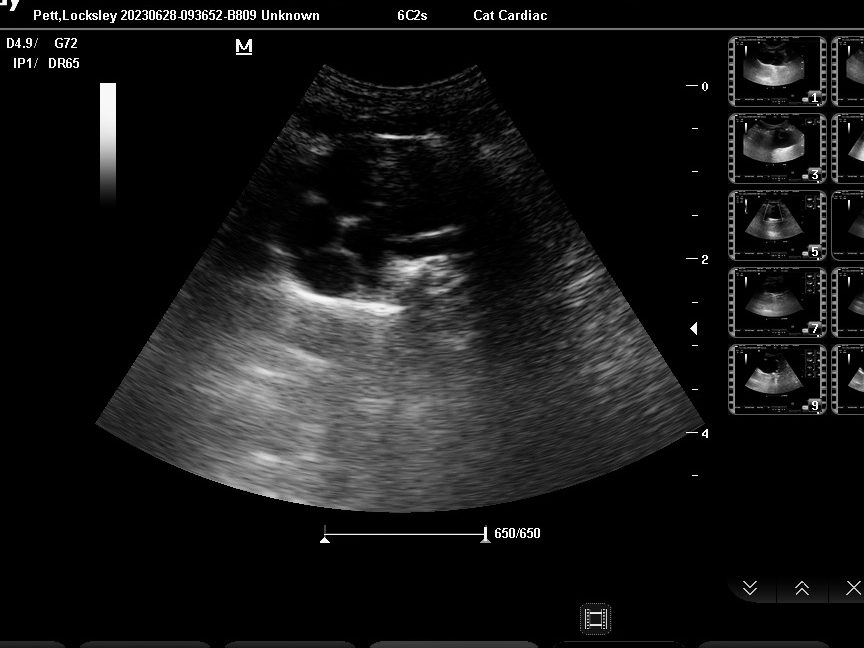

Other procedures

The only other procedure we know about is ultrasound, where there’s a picture done of your soft tissues to see how they are. This picture is of Locksley’s heart. It showed it was working properly, pumping away. I must admit I can’t see anything, and Mummy said she couldn’t really even when she had the moving image. But Dr R said his heart was working fine, so that was all right.

Mummy said both Victor the First and Humphrey had ultrasound at the Norfolk vets. Victor had a cyst on his kidney, but that wasn’t causing him any trouble. Humphrey had trouble with the valves of his heart which weren’t working properly, but the meds he took helped that just fine.